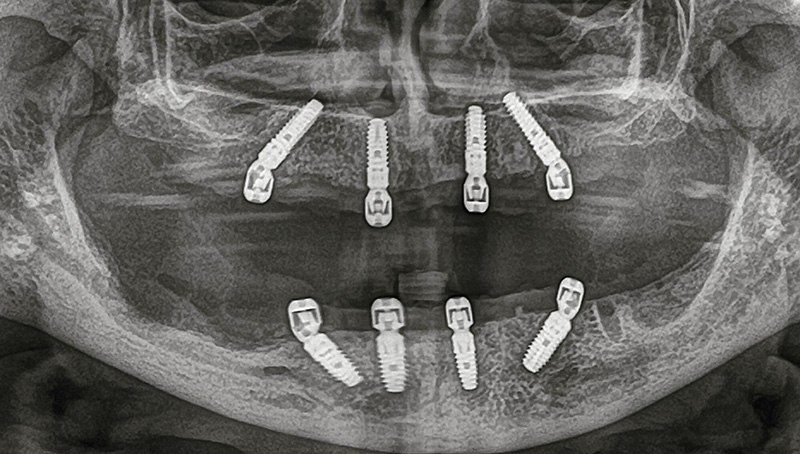

Detailed radiological evaluation (CBCT imaging)

Individual assessment of bone volume and quality